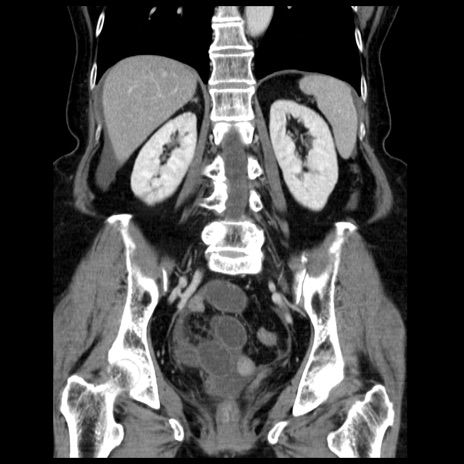

症例13(冠状断像)

【症例】70歳代女性

【主訴】腹痛、嘔吐

【現病歴】15時間程前(昨晩)より腹痛あり。今朝になっても症状の改善なく、嘔吐あり。腹痛も増悪あり、救急外来受診。

【既往歴】子宮癌全摘術後

【身体所見】意識清明、BP 121/72mmHg、P 74bpm、SpO2 100%(RA)、腹部:平坦・軟、腸雑音ほぼ聴取せず。下腹部・心窩部・臍左上に圧痛あり。反跳痛なし。

【データ】WBC 10600、CRP 0.15